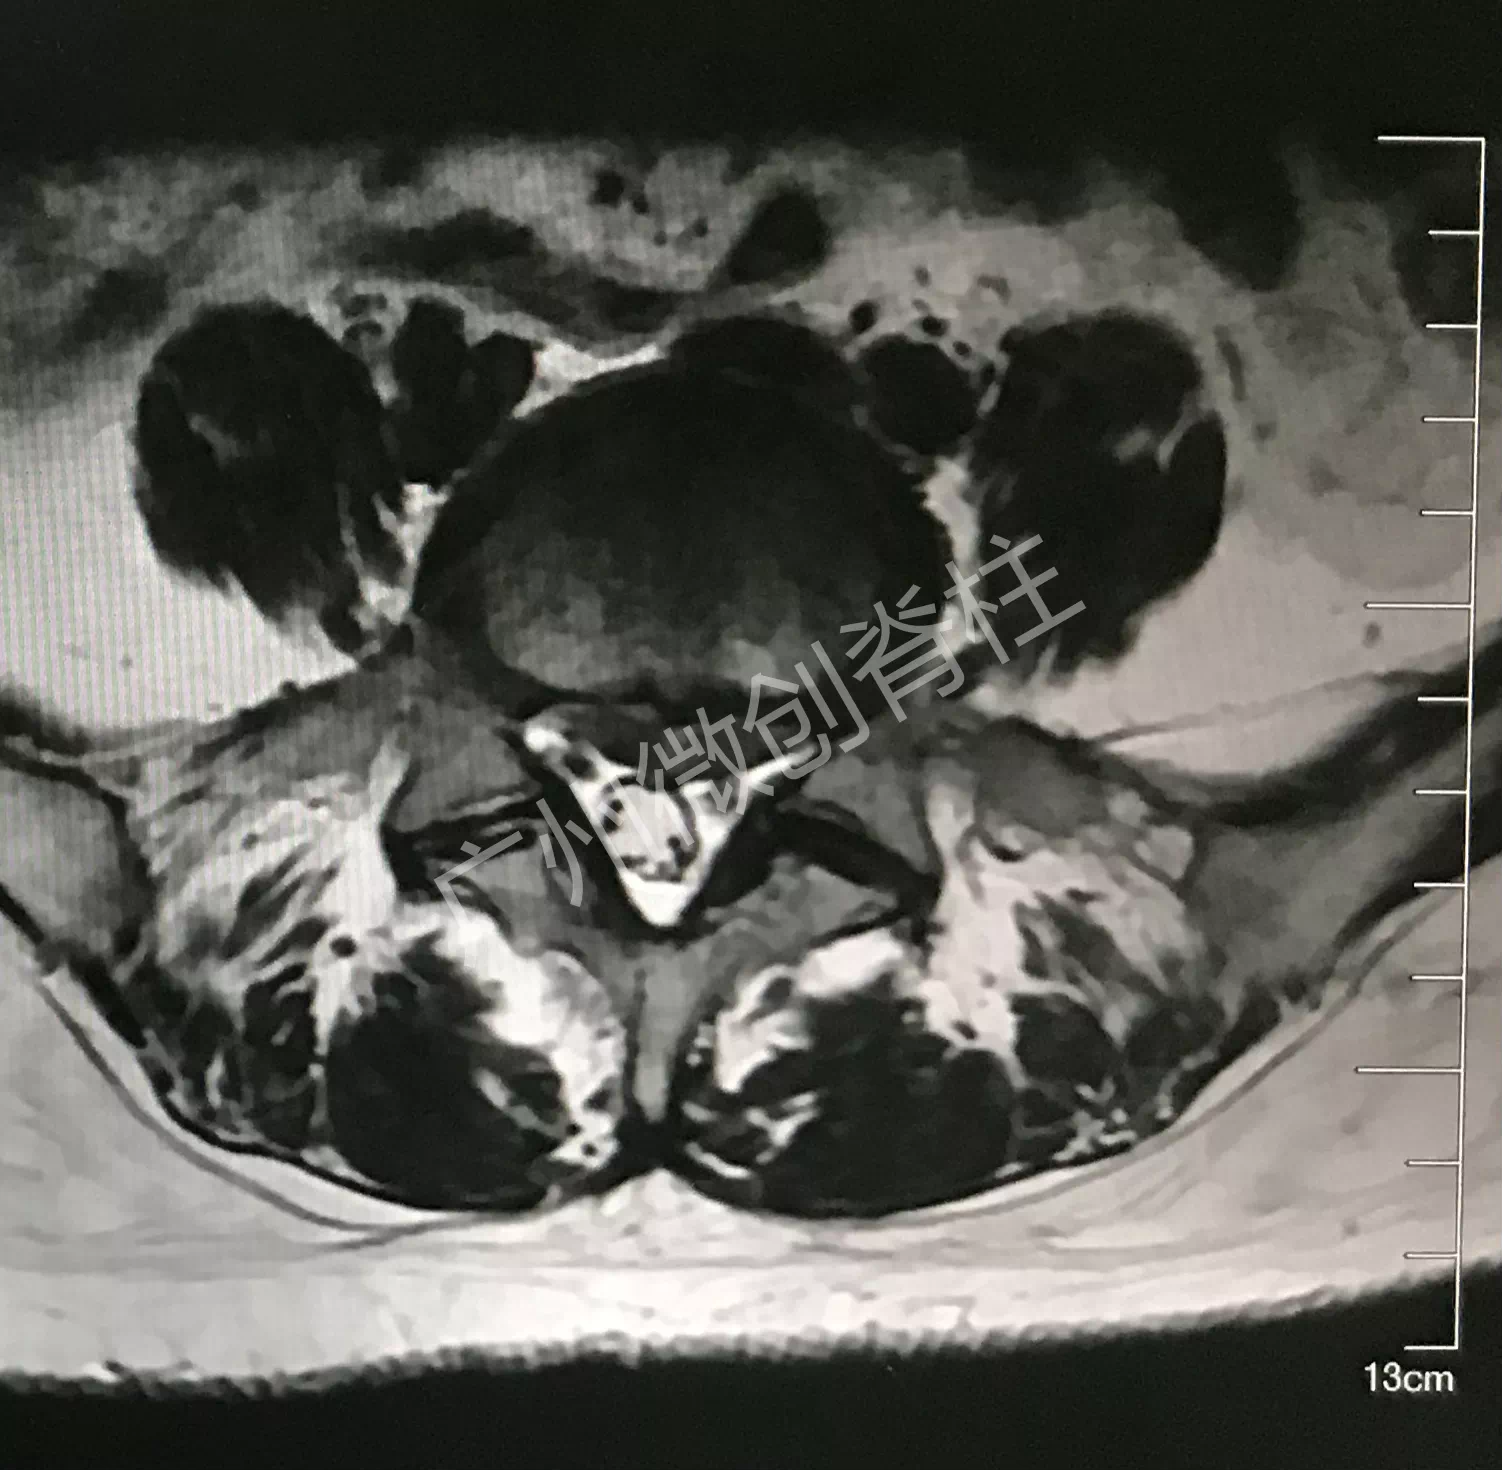

50多岁的女性患者,腰痛伴左下肢麻痛3年多,久坐或长时间行走后加重,在外院多次予按摩、针灸、贴药膏等治疗,症状未见明显好转,严重困扰日常生活及工作,为进一步诊治,遂来广州医科大学附属第一医院脊柱外科找到何二兴主任就诊,何二兴主任了解了患者病史及体征,结合x光、CT及MR检查结果,诊断为腰椎间盘突出症,患者腰5骶1节段有大块椎间盘突出,压迫神经,引起神经性疼痛。

何二兴主任治疗团队对患者的病情进行了详细的研究,决定利用微创手段,使用内窥镜辅助方法,顺利帮助患者解决了困扰3年多的痛苦。患者恢复很快,术后第一天就可以佩戴腰围下地行走。手术伤口如硬币大小,伤口愈合后疤痕挛缩伤口更小。